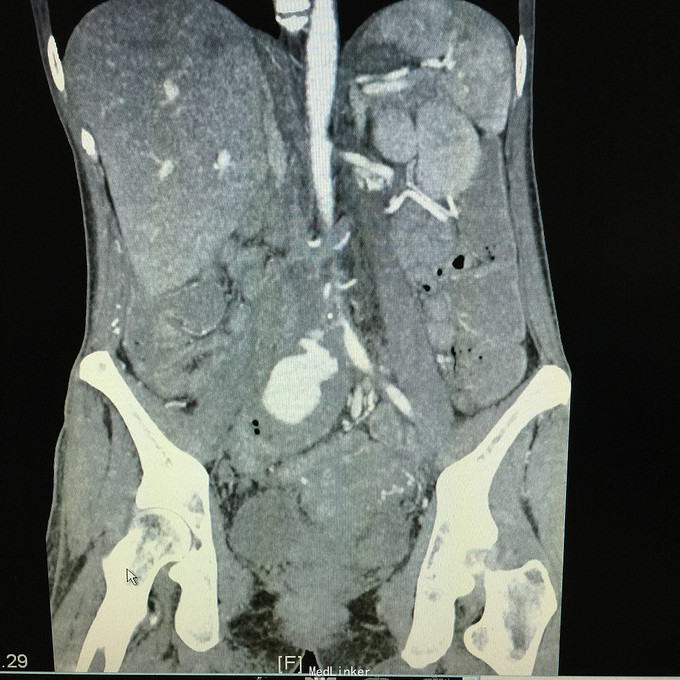

查体无特殊。 辅助检查:中下腹CT平扫+增强+CTU+CTA示:1.右输尿管中上段病变,考虑恶性病变,周围多发淋巴结转移,髂总动脉及髂外动脉起始部、髂内动脉中上段受侵闭塞,右侧腰大肌可疑受侵;建议输尿管镜检查;右肾重度积水,右肾功能明显受损。2.CTA示:右肾动脉纤细,肝右动脉起源于肠系膜上动脉。3.子宫体密度不均匀,建议MRI检查。中下腹MRI平扫+增强+MRU检查结果类似。

患者术后2月出现反复臀部疼痛,左侧为主,疼痛跑迷宫为隐痛,于翻身及活动时加重,卧床休息可稍缓解,多于下午出现,伴有发热,最高达39℃,在当地医院予“氟康唑”及止痛治疗后稍有缓解,但仍反复发热。后疼痛加剧,并出现双下肢疼痛,以大腿外侧为主,无间歇性跛行,无小腿及双足麻木疼痛不适,行对症治疗后效果不佳,于2015-10-9再次返院,予消炎止痛、营养支持及营养神经等治疗。查CT及MRI均提示骶髂关节炎症及腹膜后巨大病变,右侧髂总动脉及髂内、外动脉上段、右侧腰大肌受累。2015-10-15 14:00患者出现右下肢剧烈疼痛、右下肢乏力和麻木,随后出现2次血便,每次量约100ml,暗红色,无腹胀、腹痛等不适,查血提示白细胞 28.17*10E9/L,中性粒绝对值 25.33*10E9/L,血红蛋白56g/L,予止血、输血、抗真菌、止痛等治疗。19:00再次出现右下肢剧烈疼痛伴右下腹痛,查体:BP 80-90/50-60mmHg,P 100-106次/分,R 23次/分,SpO2 100%。右下腹轻压痛,反跳痛阴性,右下肢蹲背伸及踝背伸肌力II-III级,立即行全腹CT检查,示右髂总动脉假性动脉瘤破裂,予加强输注浓缩红细胞及补液支持治疗。清介入科会诊,考虑脓肿和感染为介入血管腔内支架置入治疗的禁忌症,建议予血管外科行开放手术,予患者及家属沟通,并转外院血管外科进一步治疗。